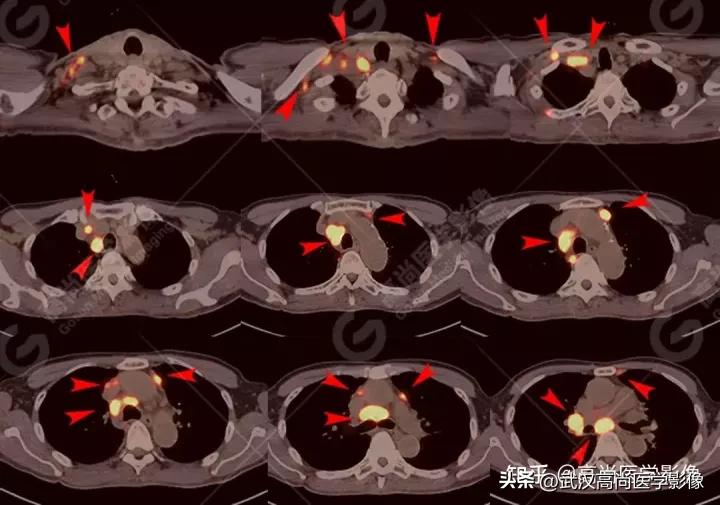

双侧锁骨区、左侧内乳区、双侧肺门、纵隔(1R、2、3A、4R、5、6、7、8、9组)、心底部、胰胃间隙多发淋巴结肿大,FDG高摄取,SUVmax16.3。

全身多处骨质成骨性破坏,FDG高摄取,SUVmax16.3。

右肺下叶背段见一实性结节,大小约2.0cm×1.6cm×1.8cm,CT值33Hu,FDG高摄取,SUVmax13.0。

右肺上叶尖段胸膜下见一实性结节,范围约1.6cm×1.3cm,病灶紧贴邻近胸膜,伴牵拉增厚,FDG高摄取,SUVmax为7.5。

恶性CT征象:

结节边缘不光整,分叶、长短不一的毛刺,邻近胸膜牵拉明显。

右侧胸膜区多发条片状代谢增高影,SUVmax4.7,CT于相应部位胸膜增厚,伴右侧中量胸水。

PET代谢增高,在发现胸膜转移较常规CT扫描有一定的优势。